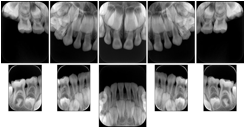

6 Standard Pedodontic A Dental Image Layout

DL-P001A

6 Standard Pedodontic B Dental Image Layout

DL-P001B

6 Standard Pedodontic C Dental Image Layout

DL-P001C

6 Standard Pedodontic D Dental Image Layout

DL-P001D

10 Standard Pedodontic A Dental Image Layout

DL-P003A

10 Standard Pedodontic B Dental Image Layout

DL-P003B